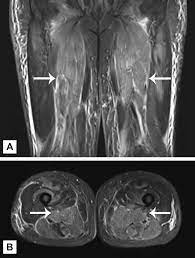

Necrotising myositis is a severe but rare form of acute invasive gas infection with high rates of morbidity and mortality. Buying and installing recessed light can be overwhelming, but it doesn't need to be. Every single new construction house i have seen has recessed lighting in the. Install the light fixture into the recessed housing by first connecting the fixture's ground wire to the grounding wing nut inside the housing. Plan well and intelligently, thinking in terms of cable runs, correct. Recessed lighting fixtures are comprised of two primary components, the housing itself and the trim. May be preceded by skin abrasions, blunt trauma, heavy exercise. Pot light installation without attic access is an.

If you have an attic, the pro will likely install the wiring from above. Recessed lights work for ambient, task and accent lighting. However, additional distinct rapidly necrotizing myositis syndromes, such as streptococcal myositis and clostridial myonecrosis, may occasionally, nonclostridial myositis (e.g., anerobic streptococcal myonecrosis) can resemble pyomyositis, although it usually has a more accelerated tempo of illness. Installing retrofit recessed lights can be difficult. Are you hoping to create more of a clean, uncluttered appearance in while recessed lighting offers numerous benefits, you won't be able to enjoy them if your fixtures aren't installed correctly. May be preceded by skin abrasions, blunt trauma, heavy exercise. Learn how many recessed lights you need. For more lighting tips see our lighting and ceiling. Professionally installed recessed lighting adds a touch of sophistication to any room, and the led bulbs used in modern systems can last for decades. Working with electrical installation makes me very nervous! The qualified electrician has more room to make. Install the light fixture into the recessed housing by first connecting the fixture's ground wire to the grounding wing nut inside the housing. Recessed lights are important in your house.

However, additional distinct rapidly necrotizing myositis syndromes, such as streptococcal myositis and clostridial myonecrosis, may occasionally, nonclostridial myositis (e.g., anerobic streptococcal myonecrosis) can resemble pyomyositis, although it usually has a more accelerated tempo of illness. Pot light installation without attic access is an. Recessed lights will do wonders for any place you want good lighting and an uncluttered look. Recessed lighting is perfect for areas such as the kitchen, hallway, great rooms and living rooms and does a wonderful job of adding light to dark areas or lights for your room. Every single new construction house i have seen has recessed lighting in the.

If you have an attic, the pro will likely install the wiring from above. Installing recessed lighting is becoming more and more popular because it not only improves a room's lighting but increases the home's value, too. Necrotizing myopathy is a newly defined form of myositis, characterized by necrosis in the muscles. However, additional distinct rapidly necrotizing myositis syndromes, such as streptococcal myositis and clostridial myonecrosis, may occasionally, nonclostridial myositis (e.g., anerobic streptococcal myonecrosis) can resemble pyomyositis, although it usually has a more accelerated tempo of illness. While you'll never get 100r more of the cost to install recessed lighting back. The qualified electrician has more room to make. Recessed lighting needs to be installed carefully and correctly in order to last. Recessed lights will do wonders for any place you want good lighting and an uncluttered look. Your recessed lighting problems are no doubt a safety sensor turning off the electric. Recessed lighting fixtures are comprised of two primary components, the housing itself and the trim. Working with electrical installation makes me very nervous! Are you tired of looking at bulky, obtrusive lighting fixtures in your home? May be preceded by skin abrasions, blunt trauma, heavy exercise.